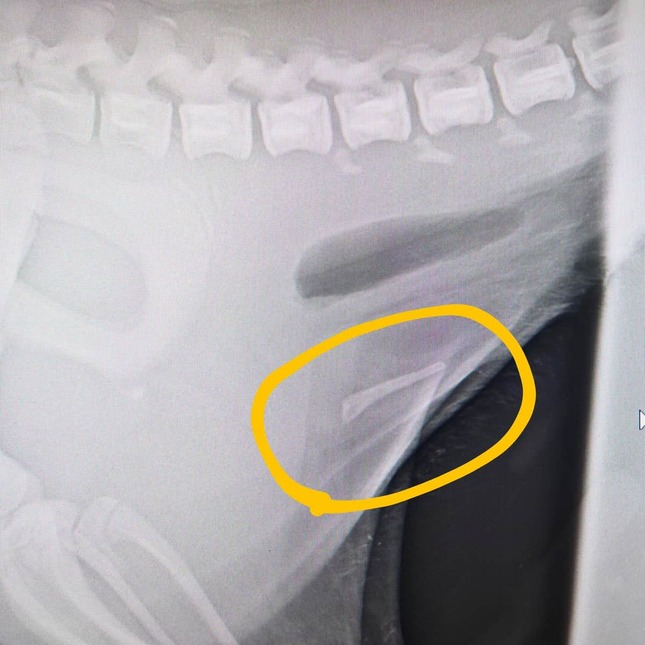

• おはぎの陰茎骨のレントゲン写真(甲府市遊亀公園附属動物園提供)

おはぎの陰茎骨のレントゲン写真(甲府市遊亀公園附属動物園提供)

「ちなみにこちらがおはぎの陰茎骨です。

ビーバーは外観では性別判断できず、オスには陰茎骨という骨があるため、レントゲン等で検査します。

今後はさらに慎重に検査をしてまいります。

お騒がせしてしまい、申し訳ありません」